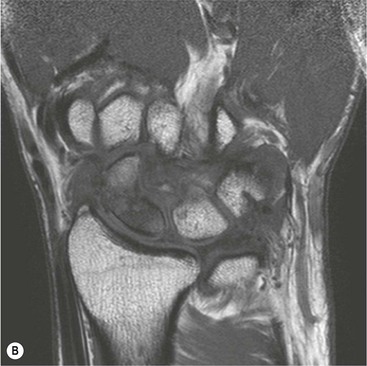

Abnormal communication between the radiocarpal and midcarpal joints may be seen on arthrography (Fig. 46-28), which is usually combined with MRI or CT16 (Figs. 46-29 and 46-30). However, direct visualisation of the ligaments is possible with conventional MRI. The most important features to describe that help determine management include the following:

The TFC is composed of fibrocartilage and is normally low SI on all MRI pulse sequences (Fig. 46-31). Tears of the TFC complex may present as ulnar-sided wrist pain. They occur as either a degenerative phenomenon or as an acute injury. Degenerative tears frequently result in central perforation of the TFC (Fig. 46-32), and are associated with positive ulnar variance (long ulna). This in turn may lead to ulnar abutment on the triquetrum, which is another cause of ulnar-sided wrist pain.